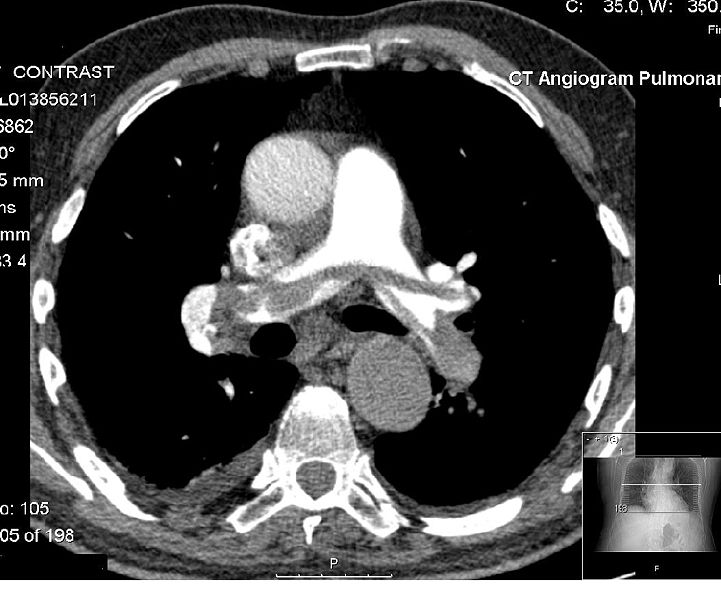

The cause is usually a blood clot in the leg called deep vein thrombosis. Large saddle embolus seen in the pulmonary artery (white arrows). Less than 5 to 10% of symptomatic pes are fatal within the first hour of symptoms. Massive and submassive pulmonary emboli (pe) are rare but. Saddle pulmonary embolism diagnosed by ct angiography: If the main pulmonary artery is involves where blood flow is occluded to both lungs, it is called a saddle embolus, and requires immediate removal. A pulmonary embolism is a sudden blockage in a lung artery. It demonstrated a central saddle embolism and multiple occlusive and . Tumor, air, and fat emboli are discussed separately. Once a clot has formed in the deep veins of the leg, . Saddle pulmonary embolism commonly refers to a large pulmonary embolism that straddles the bifurcation of the pulmonary trunk, extending into the left and . This is called deep vein thrombosis (dvt). Saddle pulmonary emboli (pe) are clots that straddle the bifurcation of the left and right main pulmonary arteries.

The cause is usually a blood clot in the leg called deep vein thrombosis. Tumor, air, and fat emboli are discussed separately. A pulmonary embolism is a sudden blockage in a lung artery. Large saddle embolus seen in the pulmonary artery (white arrows). Saddle pulmonary embolism diagnosed by ct angiography:

Saddle pulmonary embolism diagnosed by ct angiography: This is called deep vein thrombosis (dvt). Tumor, air, and fat emboli are discussed separately. If the main pulmonary artery is involves where blood flow is occluded to both lungs, it is called a saddle embolus, and requires immediate removal. The cause is usually a blood clot in the leg called deep vein thrombosis. Saddle pulmonary embolism commonly refers to a large pulmonary embolism that straddles the bifurcation of the pulmonary trunk, extending into the left and . Large saddle embolus seen in the pulmonary artery (white arrows). Massive and submassive pulmonary emboli (pe) are rare but.

Venous clots most often happen in the deep veins of the legs. The cause is usually a blood clot in the leg called deep vein thrombosis. This is called deep vein thrombosis (dvt). Saddle pulmonary embolism commonly refers to a large pulmonary embolism that straddles the bifurcation of the pulmonary trunk, extending into the left and . Large saddle embolus seen in the pulmonary artery (white arrows).